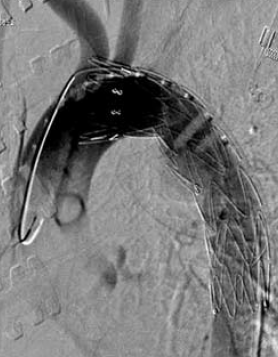

11. ábra.

A stent graft beültetés során végzett DSA az aortasérülés okozta álaneurysmát mutatja.

12. ábra.

A stent graft beültetése után az aorta kontúrja kiegyenlített, az álaneurysma szájadéka lefedésre került.

Neurológiai vizsgálattal petyhüdt alsó végtagi paraplegia volt kimutatható. Tudata visszatért. 24 órán belül, keringési paramétereinek stabilizálása után, stent graft implantatiot, majd másnap ThX-LII segmentumban transpedicularis gerincrögzítést végeztünk (10.,11., 12. ábra). Paraplegia mellett lábszártörését egy héttel később lemezes osteosynthesissel oldottuk meg. A postoperativ szakban septicus szövődmények alakultak ki mind lágyrész sérüléseinek mind gerincműtétének területén. Hosszas antibiotikus kezelés mellett septicus állapota rendeződött. Parapareticus állapotban került vissza a beküldő kórházba rehabilitatio céljából. A betegek és ellátásuk adatainak összefoglalását I, II és III táblázat mutatja.